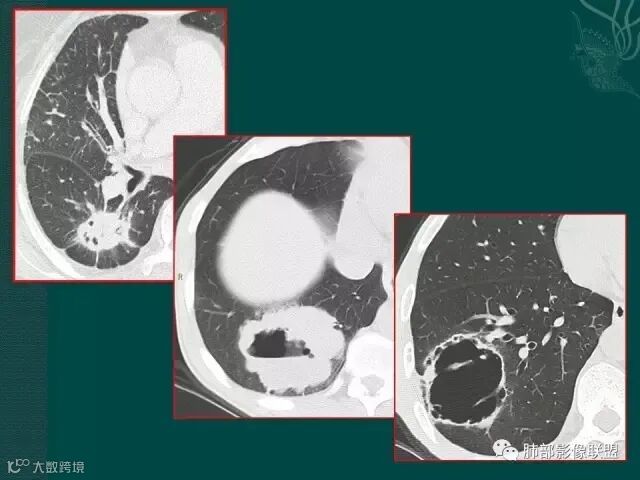

第二个是典型的肺癌坏死后形成的厚壁空洞;

第三个也可以称为空洞,但和第二个不完全相同,壁较薄,内有分隔,我们也称为假性空洞,是支气管活瓣作用形成的,我们也称为假大空。

上一个是磨玻璃密度肺癌,边缘清晰,内有分隔,空洞型肺癌伴磨玻璃密度影的,100%为腺癌,很显然这是个假性空洞;

下一个也是肺癌,内有分隔,外下缘箭头所示也是磨玻璃影,这也是腺癌,同时可见叶间裂有转移灶。